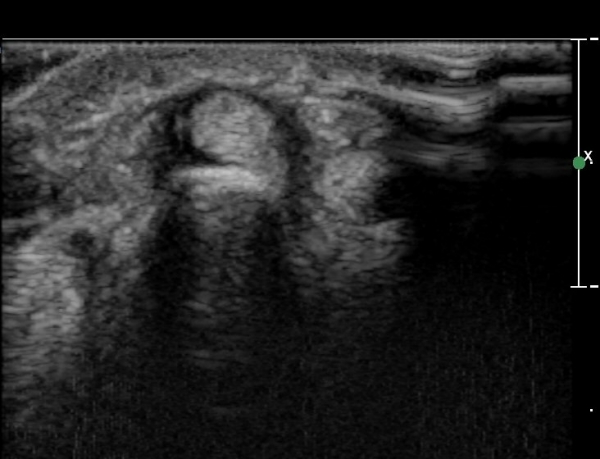

ŽÃËÀÚ¸¦ ¾à°£ ¸»´ÜÀ¸·Î À̵¿ÇÏ´Ï ´Ü¹«Áö½ÅÀü°Ç(EPB)ÀÇ ºÎÁ¾ ¹×°ÇÁÖÀ§ ¼ö¾×Àú·ù°¡ °üÂûµÊ(»çÁø 3)